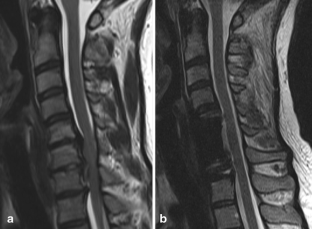

Fig. 1